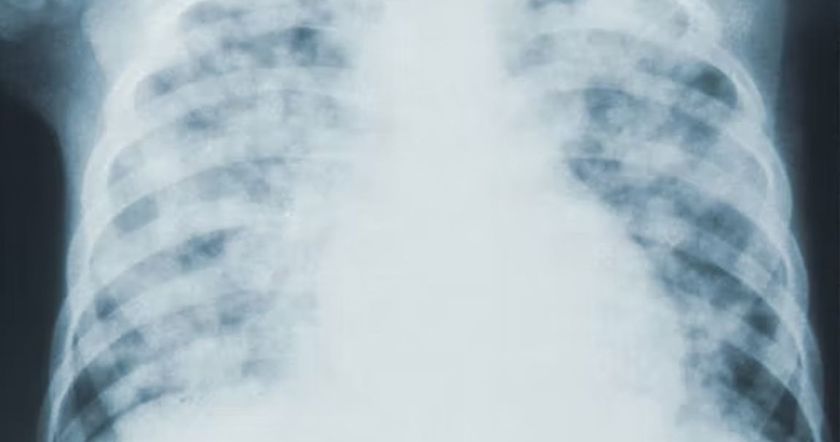

В интервью Исакова рассказала, что рак легкого может проявляться разными симптомами, порой – нетипичными.

Что касается более очевидных и известных симптомов этого вида рака – кашля, боли в груди, одышки, осипшего голоса – они чаще возникают на последних этапах заболевания.